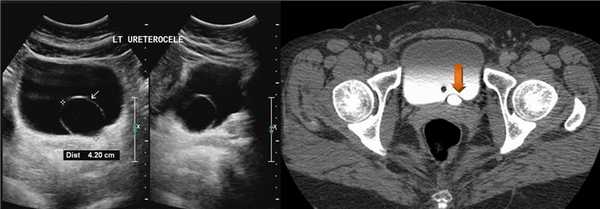

На УЗИ в мочевом пузыре или в уретре определяется анэхогенное образование, округлой формы, с четким и ровным контуром; соответствующий мочеточник обычно заметно расширен; может присутствовать гидронефроз верхней части удвоенной почки. Уретероцеле определяют как внутрипузырные (полностью внутри мочевого пузыря) или внепузырные (некоторая часть постоянно расположена в шейке мочевого пузыря или в уретре).

Рисунок. У новорожденного на УЗИ почек определяется гидронефроз (1) и расширенный мочеточник (2) справа. В мочевом пузыре двустороннее уретероцеле (3). При исследовании левой почки структурных изменений не выявлено.

Рисунок. Уретероцеле (стрелка) на УЗИ и КТ.

Рисунок. Дистальный отдел мочеточника расширен, в мочевом пузыре анэхогенное образование с тонким и ровным контуром — уретероцеле.